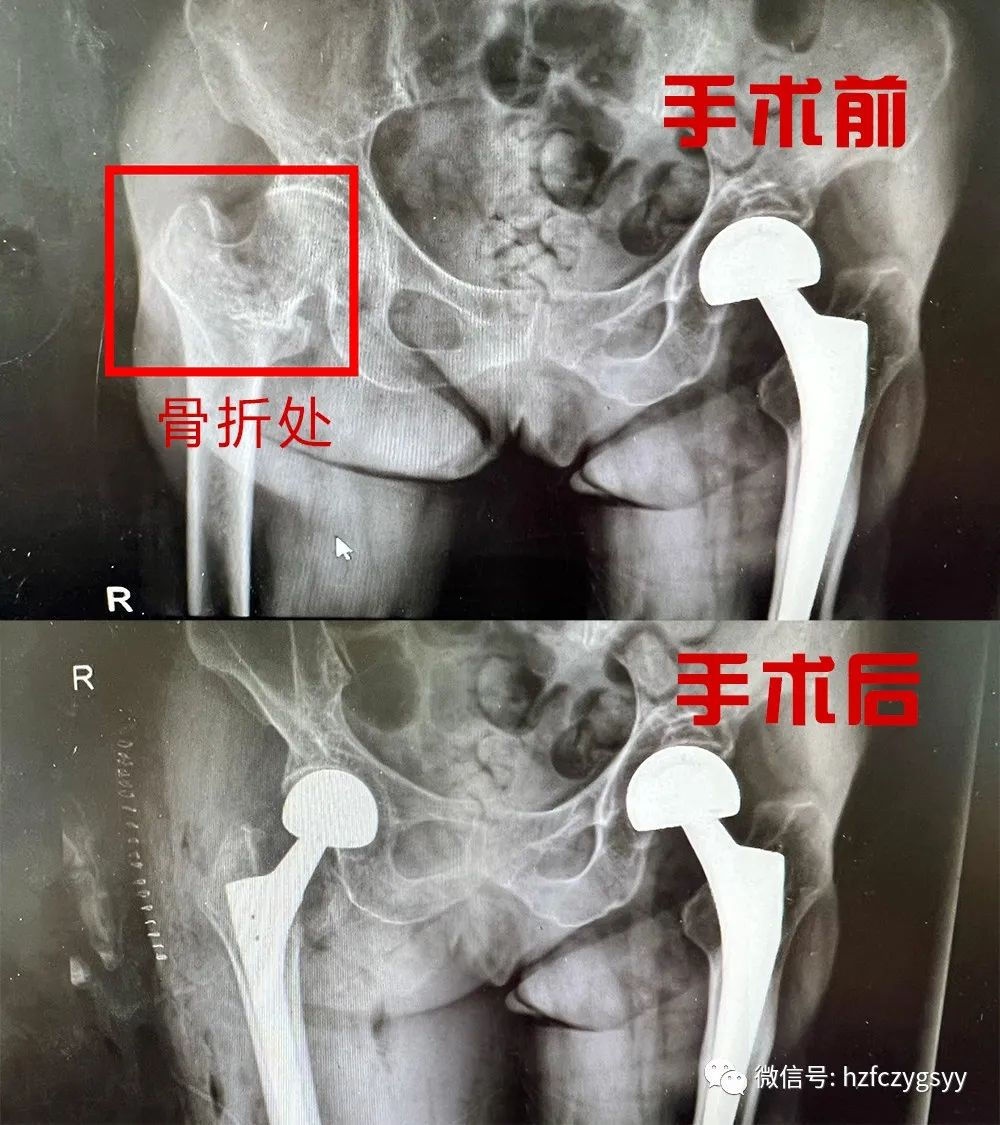

骨折部位术前术后对比

经检查诊断为:右股骨颈基底部骨折,家人得知老太太骨折后都比较着急,并表示一定会配合治疗,希望尽早安排手术。住院医生了解病人迫切的需求后立即请骨伤三病区(创伤、关节病区)吴勇成主任进行会诊,并确定治疗方案。

8月15日下午在腰硬联合麻醉下,结合患者年龄以及受伤情况,骨伤三病区吴勇成主任团队给患者行右股骨颈基底部骨折人工股骨头置换术,通过2个多小时的奋战,手术终于顺利完成,家属和患者都对吴勇成主任的技术给予高度肯定,现在患者继续在我院骨伤科三病区安心养伤,一般6-8周后可以正常恢复活动。